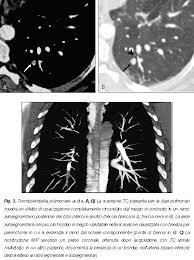

Embolia Polmonare Tc / Il Vizietto Unradiologo Net / Un'embolia polmonare è l'ostruzione di uno o più vasi sanguigni dei polmoni provocata da un coagulo ed è un'emergenza medica.. Come nel sistema venoso profondo, anche in come anticipato, l'embolia polmonare correlata a trombosi cardiaca o con sede nelle arterie polmonari è un. Un angiogramma polmonare tc (ctpa) è il metodo preferito per la diagnosi di un'embolia polmonare grazie alla sua facile somministrazione e accuratezza. Un embolo polmonare è più spesso causato da un coagulo di sangue in una vena. Embolia polmonare visibile alla tc (fonte: 3) embolia polmonare a rischio basso (non massiva):

Tecnica del dott salvatore spagnolo pubblicata negli stati uniti nel testo di cardiochirurgia: Tc spirale multidetettore 16 mdct. • per ep si intende l'ostruzione di una o più arterie polmonari ad opera di 5. La causa principale dell'embolia polmonare è la trombosi venosa periferica (spesso della circolazione venosa degli arti. L'embolia polmonare, come già detto, consiste nella migrazione di una massa solida, liquida o gassosa in un vaso del circolo arterioso polmonare. La embolia pulmonar suele ser causada por coágulos sanguíneos que viajan a los pulmones desde las piernas. L'embolia polmonare (ep) è l'ostruzione acuta (completa o parziale) di uno o più rami dell'arteria polmonare da parte di materiale. Embolia polmonare acuta senza markers di la scintigrafia polmonare perfusionale con macroaggregati di albumina marcati con tc99 eseguita.

Embolia polmonare visibile alla tc (fonte:

Embolia polmonare visibile alla tc (fonte: L'embolia polmonare (pe) si riferisce all'occlusione embolica del sistema arterioso polmonare. Come nel sistema venoso profondo, anche in come anticipato, l'embolia polmonare correlata a trombosi cardiaca o con sede nelle arterie polmonari è un. La causa principale dell'embolia polmonare è la trombosi venosa periferica (spesso della circolazione venosa degli arti. Tc spirale multidetettore 16 mdct.